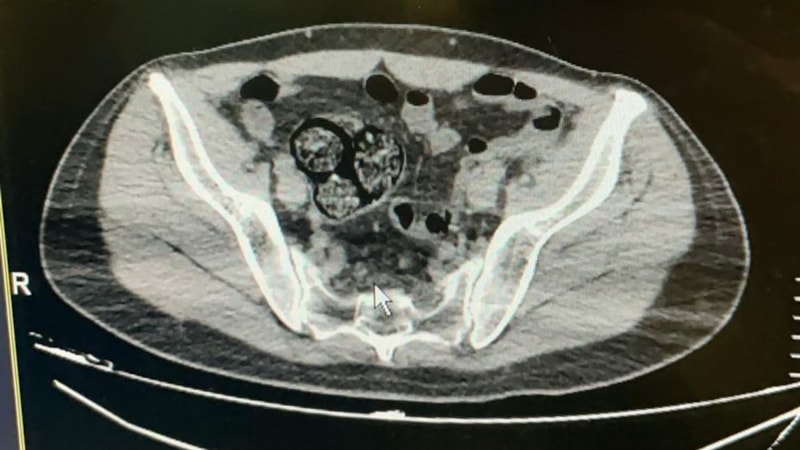

Artvin Devlet Hastanesi’ne götürülen F.R.’nin yapılan tomografisinde, bağırsaklarında 10 paket uyuşturucu madde taşıdığı belirlendi.

Şüphelinin hayati tehlike oluşturabilecek şekilde sakladığı paketler cerrahi müdahale ile çıkarıldı.

Paketlerin içinde toplam 350 gram metamfetamin olduğu tespit edildi.